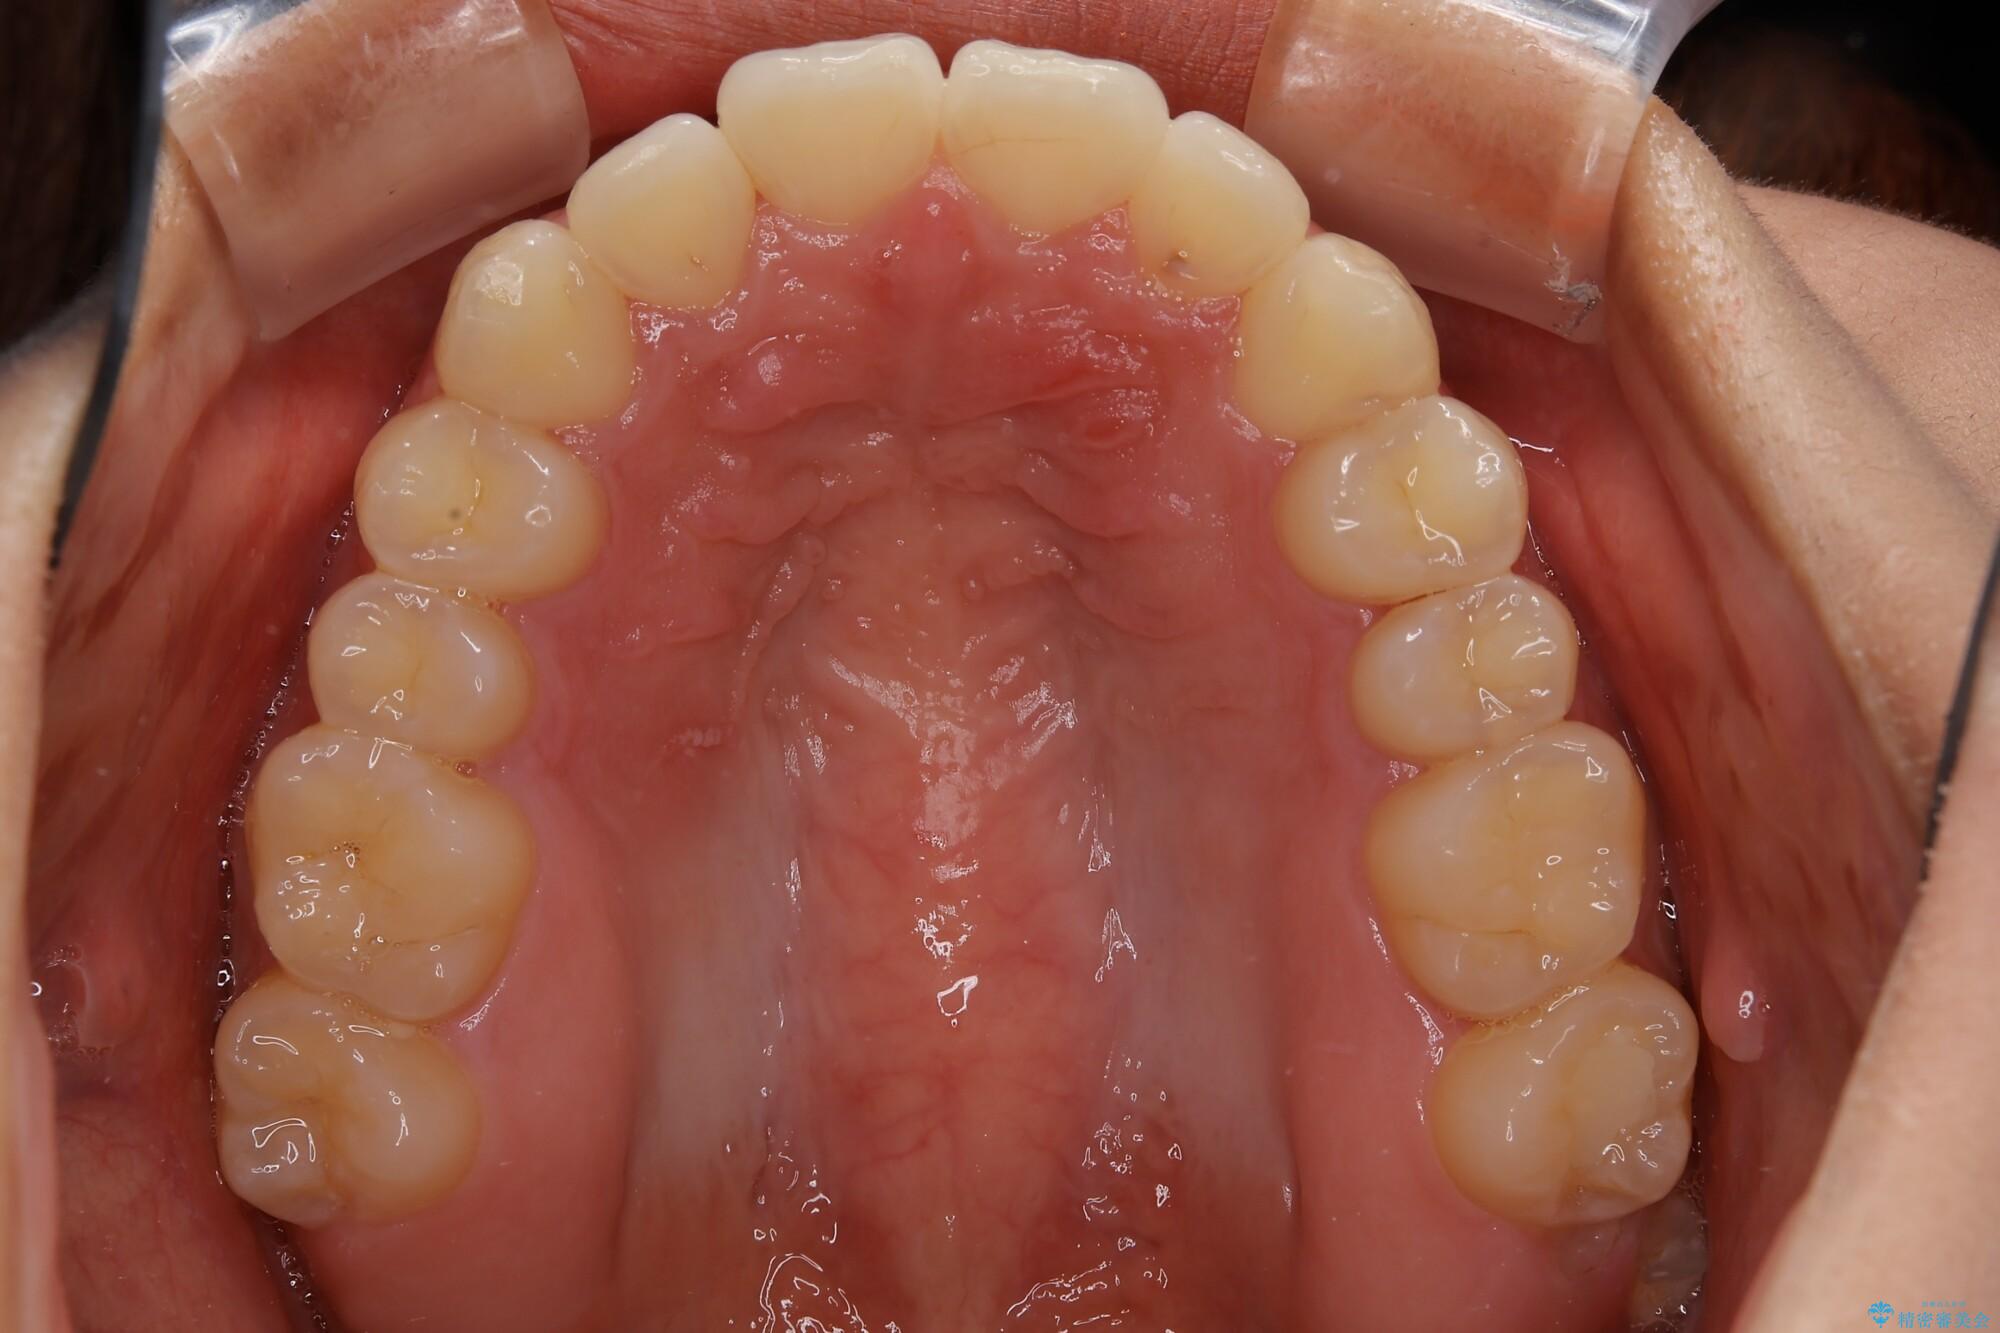

インビザライン矯正 短期間で出っ歯を改善

- 前歯が前に出ていることが気になるとのことで来院されました。

上顎の前歯が一本、唇側出ていることで、口元の突出があると感じているとのことでした。

奥歯の咬み合わせは特に問題がなかったため、上下顎の前歯のがたつきを、歯の側面を削ることで改善する治療計画としました。

この症例の患者様は、口元の突出感が気になるとのことでしたが、歯を抜く必要性がないと判断し、歯を抜かずに治療を行いました。前歯の角度を改善することで、口元が気にならなくなったと満足いただけました。